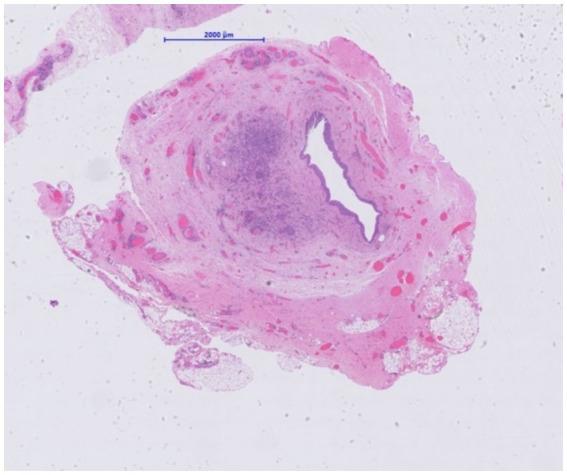

Tissue-invasive cytomegalovirus (CMV) disease represents a well-recognized complication after kidney transplantation. However, direct involvement of the urogenital tract and CMV-ureteritis occur less frequently. Nephrogenic adenomas are benign lesions of the urinary tract preferentially reported in kidney transplant recipients. We herein report a second case of a 33-year-old male kidney transplant recipient with acute post-renal allograft dysfunction due to CMV-positive ureteral nephrogenic adenoma. A causal connection might be suspected but remains to be proven.

组织侵袭性巨细胞病毒(CMV)病是肾移植后一种公认的并发症。然而,泌尿生殖道直接受累及CMV输尿管炎的情况较少见。肾源性腺瘤是尿路的良性病变,在肾移植受者中报道较多。我们在此报告第二例33岁男性肾移植受者,因CMV阳性输尿管肾源性腺瘤导致急性肾移植术后肾功能不全。可能怀疑存在因果关系,但仍有待证实。